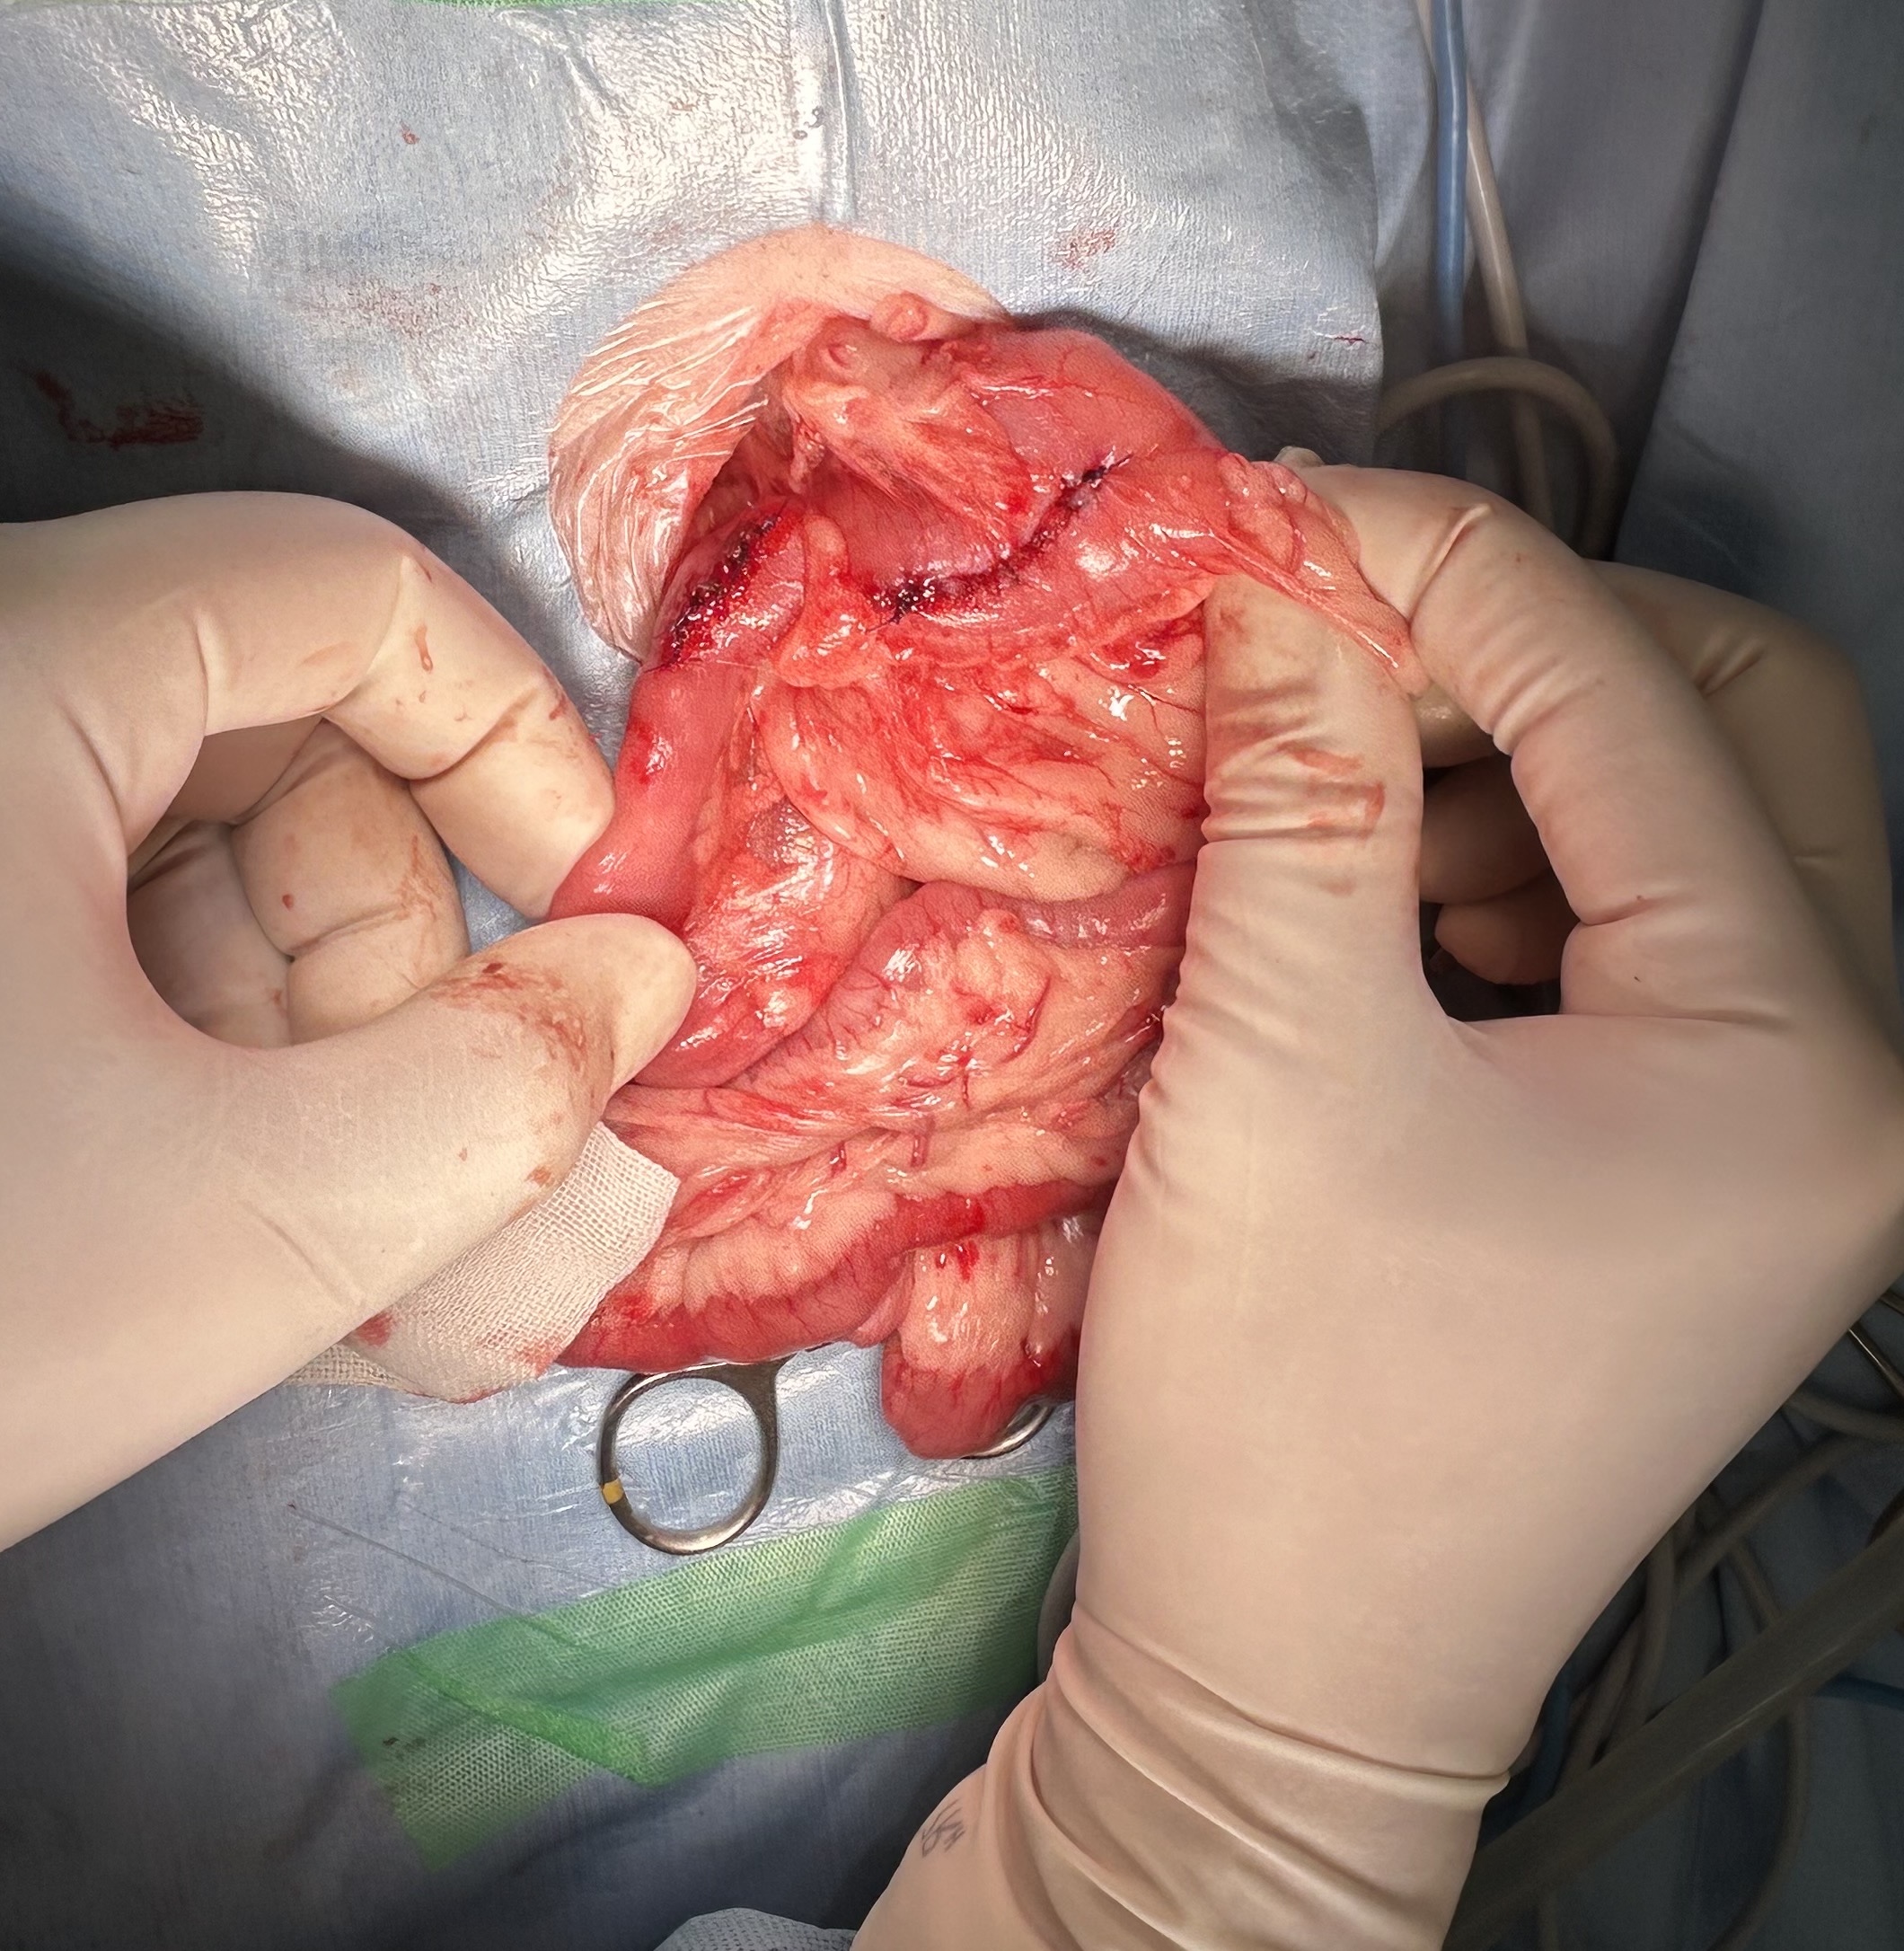

腸内の紐状異物は、動物が誤って糸や紐、ビニールテープなどを誤飲した場合に、腸に引っかかってアコーディオン状に手繰り寄せられる非常に危険な状態です

重度の腸閉塞や腸管が裂け腹膜炎などを引き起こし、通常緊急手術が必要となります

開腹手術にて胃切開し、十二指腸切開にて釣り針についていた糸を摘出した